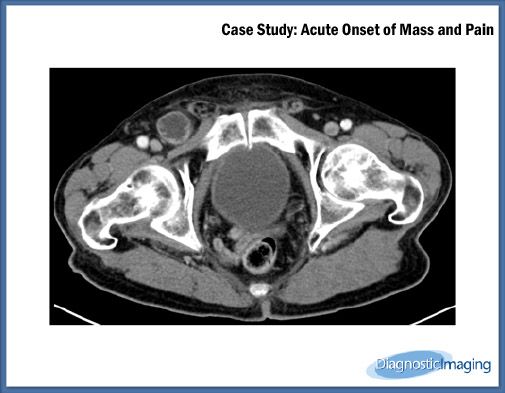

Case History: 82-year-old male presented with acute onset of right inguinal region mass.

Case History:Â 82-year-old male presented with acute onset of right inguinal region mass and pain and generalized abdominal pain.